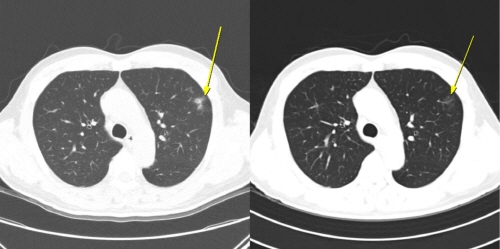

[그림1] 무증상 일시적 면역관련 폐렴 사례

[그림1] 무증상 일시적 면역관련 폐렴 사례: 이 환자는 AteBeva 치료 3개월째 시행한 저선량 흉부 CT(왼쪽)에서 폐 주변부에 미세 염증성 음영이 나타났으나, 6개월째 CT(오른쪽)에서는 자연적으로 소실되는 양상을 보였다. 치료는 지속됐으며,이후 부분 관해(PR)를 달성했고 총 19.7개월간 무진행 생존(PFS)을 유지했다.